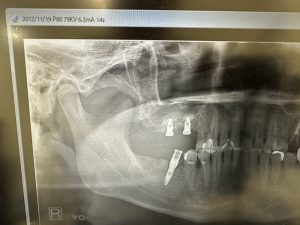

右側は約14年経過、安定している💪